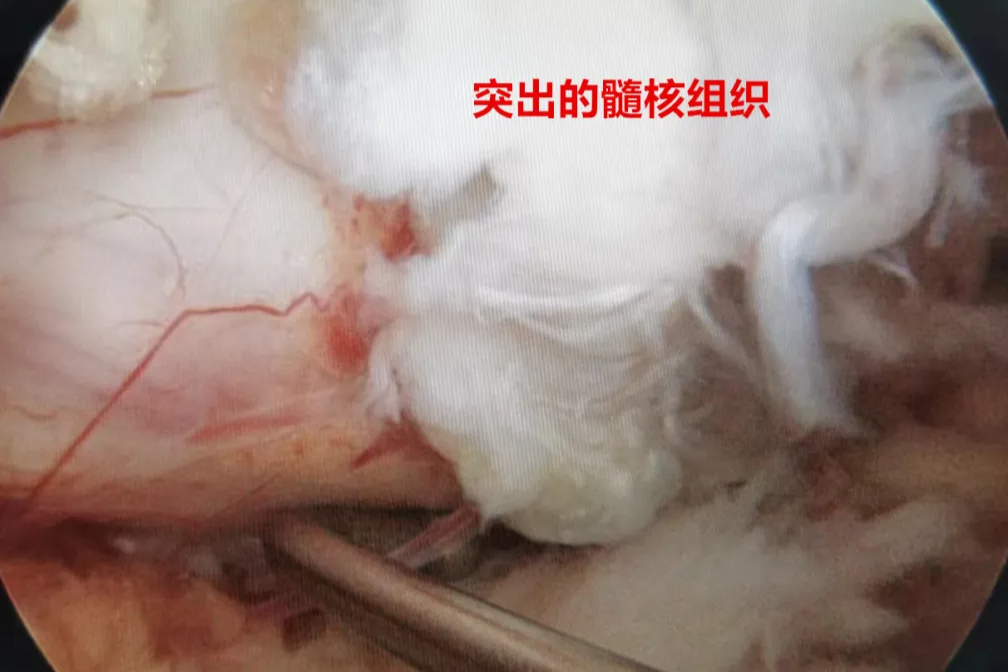

但同时,黎华文也告诉苏阿姨,这种骶前肿瘤,在过去被视为「手术禁区」,主要来源于腹膜后间隙的脂肪、疏松结缔组织、筋膜、肌肉、血管、神经、淋巴组织以及胚胎残留组织,发病率占全身各类肿瘤不足 0.5%。该类肿瘤位置较深、发病隐匿,常常在肿瘤巨大、侵犯或挤压周围脏器发生合并症时才被发现。

手术切除是该肿瘤的主要治疗手段。但同时因为肿瘤位于骶骨前腹膜后,位置深、骶前静脉丰富,剥离肿瘤过程中极容易出现无法控制的静脉窦出血,术中出血风险极大,手术难度极高,做这样一台手术就是打一场硬仗!

专家讨论认为,腹膜后肿瘤直径超过 10 cm,并且位于骶前,与骶前静脉丛关系密切,肿瘤右侧压迫右侧髂内动静脉,手术难度大、风险高。但肿瘤边界尚清楚,未见明显的骨质侵犯,手术关键是解剖清楚、控制好出血。

妇科主任黎华文、脊柱骨病科主任秦毅、心胸外科主任李明指导,副主任医师马中原等在台上通力合作,经过 5 小时 40 分的战斗,晚上 8 点零 5 分,手术顺利结束,困扰苏阿姨大半年的腹膜后炸弹终于被拆除,术中出血约 1000 ml,术后病检结果提示神经鞘瘤。